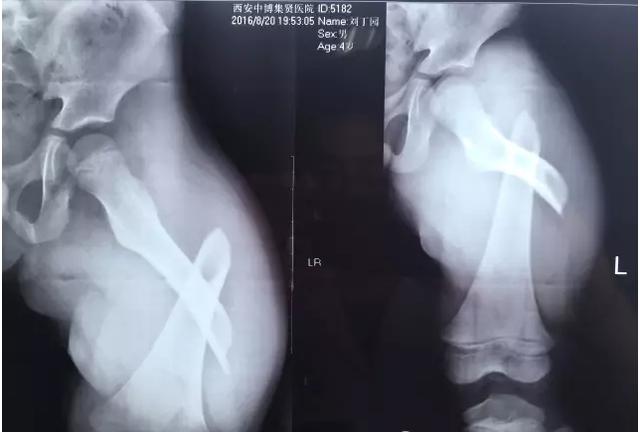

專家表示,大部分骨折是跌倒引起的,最多見的就是骨質疏松性骨折,主要包括橈骨遠端、肱骨近端、胸腰椎骨折和髖部骨折。

“許多人跌倒后的第一反應是手撐地,導致摔倒的力量經(jīng)手腕傳導至前臂,從而形成橈骨遠端骨折。”北京積水潭醫(yī)院新街口院區(qū)創(chuàng)傷骨科副主任醫(yī)師王陶說,如果是髖部骨折,對高齡老人而言,風險和危害更大。